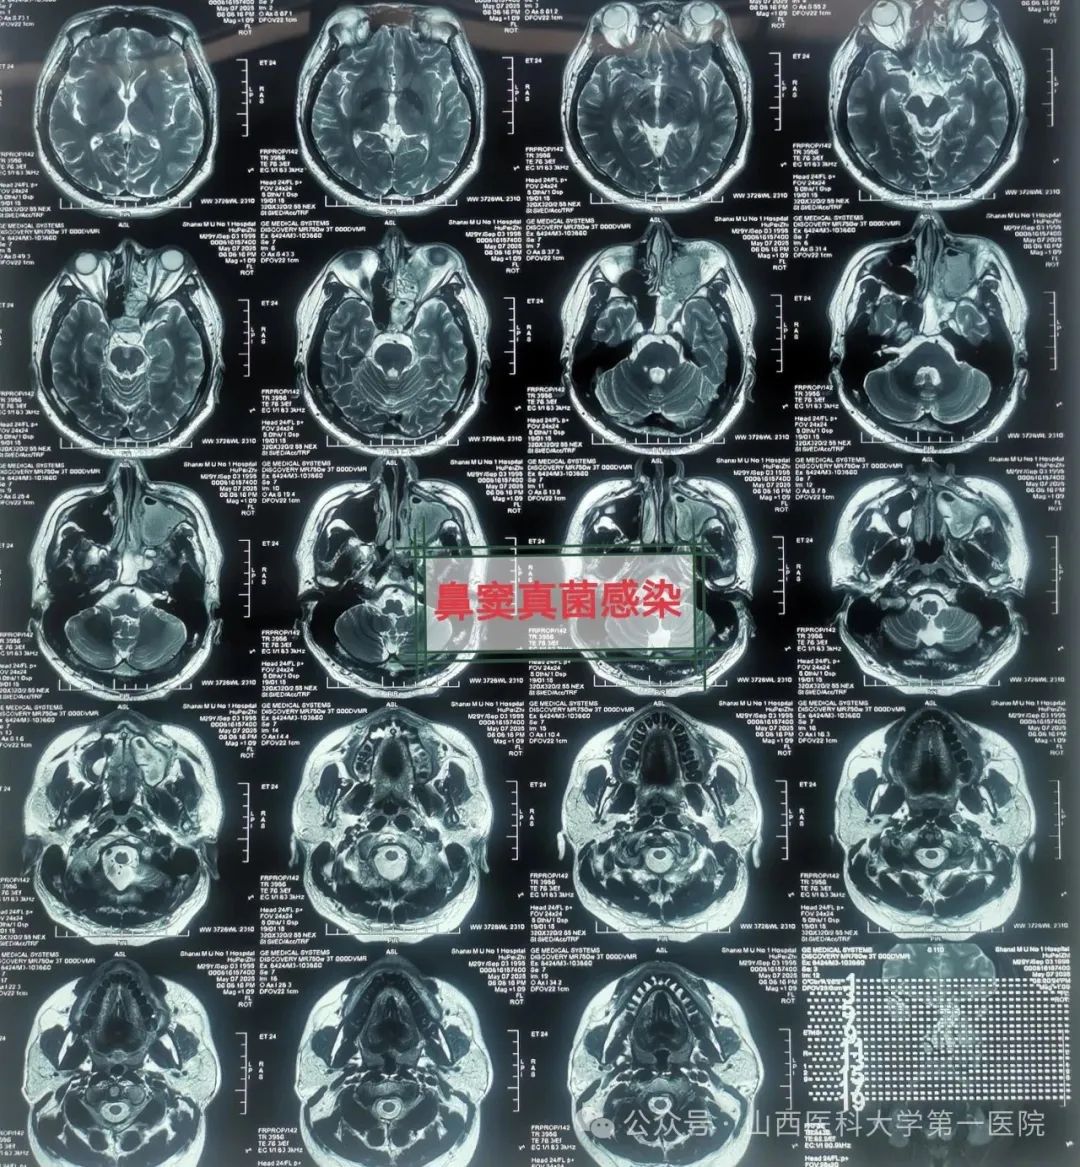

49岁的袁先生过敏性鼻炎多年,合并糖尿病与痛风,一直药物维持治疗;2年前因合并鼻窦炎,口服药物治疗效果不佳;近数月以来病情逐渐加重,鼻塞流涕,最近头痛头闷症状越来越严重同时出现鼻涕带血丝,就诊于东京热

耳鼻咽喉-头颈外科,确诊为鼻窦真菌感染,医生通过手术切除鼻腔病变组织,清除霉菌团块,开放鼻窦,引流分泌物,清洗术腔,重建鼻腔结构、恢复功能,改善并缓解了临床症状。

耳鼻咽喉-头颈外科皇甫辉教授介绍,真菌性鼻窦炎是临床常见的特异性感染性疾病,近年来发病率有上升趋势,可能与抗生素广泛使用、环境污染等有关,而糖尿病、抗肿瘤药物治疗、放疗以及长期使用激素等是真菌性鼻窦炎的高发人群。真菌性鼻窦炎通常分非侵袭型真菌性鼻-鼻窦炎与侵袭型真菌性鼻-鼻窦炎两类,非侵袭型真菌性鼻-鼻窦炎之病变局限在鼻窦腔内,粘膜和骨壁内却无真菌侵犯;而侵袭型真菌性鼻-真窦炎是真菌感染不仅位于鼻腔,同时侵犯鼻窦粘膜和骨壁,并向鼻窦外周围结构和组织如眼眶、前颅底或翼腭窝等侵袭发展,一般情况下,侵袭型真菌性鼻-真窦炎预后凶险。